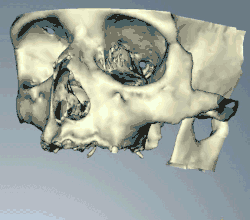

Success or failure of implants depends primarily on the thickness and health of the bone and gingival tissues that surround the implant, but also on the health of the person receiving the treatment and drugs which affect the chances of osseointegration. The amount of stress that will be put on the implant and fixture during normal function is also evaluated. Planning the position and number of implants is key to the long-term health of the prosthetic since biomechanical forces created during chewing can be significant. The position of implants is determined by the position and angle of adjacent teeth, by lab simulations or by using computed tomography with CAD/CAM simulations and surgical guides called stents. The prerequisites for long-term success of osseointegrated dental implants are healthy bone and gingiva. Since both can atrophy after tooth extraction, pre-prosthetic procedures such as sinus lifts or gingival grafts are sometimes required to recreate ideal bone and gingiva.

When a more exacting plan is needed beyond clinical judgment, the dentist will make an acrylic guide (called a stent) prior to surgery which guides optimal positioning of the implant. Increasingly, dentists opt to get a CT scan of the jaws and any existing dentures, then plan the surgery on CAD/CAM software. The stent can then be made using stereolithography following computerized planning of a case from the CT scan. The use of CT scanning in complex cases also helps the surgeon identify and avoid vital structures such as the inferior alveolar nerve and the sinus.[30][31]: 1199